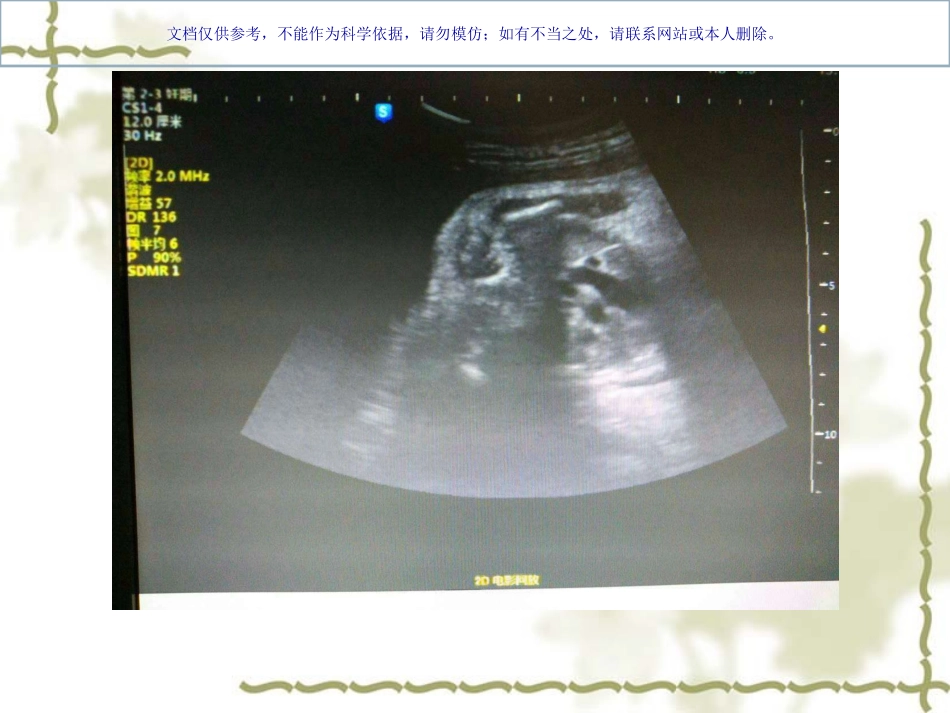

文档仅供参考,不能作为科学依据,请勿模仿;如有不当之处,请联系网站或本人删除。临床资料女27岁G1P0否认传染病及遗传病史孕30周常规产检胎儿超声检查三维及胎心检查未见异常其他实验室检查未诉异常文档仅供参考,不能作为科学依据,请勿模仿;如有不当之处,请联系网站或本人删除。文档仅供参考,不能作为科学依据,请勿模仿;如有不当之处,请联系网站或本人删除。文档仅供参考,不能作为科学依据,请勿模仿;如有不当之处,请联系网站或本人删除。文档仅供参考,不能作为科学依据,请勿模仿;如有不当之处,请联系网站或本人删除。文档仅供参考,不能作为科学依据,请勿模仿;如有不当之处,请联系网站或本人删除。永存左上腔?文档仅供参考,不能作为科学依据,请勿模仿;如有不当之处,请联系网站或本人删除。永存左上腔(PLSVC)是胎儿期最常见的先天性体循环静脉畸形正常人群中0.3-0.5%,先心中12%(畸形?变异?)文档仅供参考,不能作为科学依据,请勿模仿;如有不当之处,请联系网站或本人删除。胎儿静脉系统演变(部分)总主静脉:两侧总主静脉是胎儿最大的体静脉,右总主静脉发育形成上腔静脉,左总主静脉及其分支大部分蜕变(逐渐退化),部分残留形成冠状静脉窦。文档仅供参考,不能作为科学依据,请勿模仿;如有不当之处,请联系网站或本人删除。文档仅供参考,不能作为科学依据,请勿模仿;如有不当之处,请联系网站或本人删除。多数对血流动力学无影响,出生后无临床症状,少数?但这种畸形会增加心导管检查、起搏器植入及心脏外科手术的难度和风险。常合并心内外的畸形(内脏范围综合征)出生后常规心脏检查难以发现临床意义文档仅供参考,不能作为科学依据,请勿模仿;如有不当之处,请联系网站或本人删除。永存左上腔分型Ⅰ型:经冠状静脉窦引流入右心房(90%)Ⅱ型:经冠状静脉窦引流入右心房,但与左心房间有短路(部分右向左分流)Ⅲ型:直接引流入左心房Ⅳ型:冠状静脉窦闭锁,左上腔连接于左肺静脉文档仅供参考,不能作为科学依据,请勿模仿;如有不当之处,请联系网站或本人删除。文档仅供参考,不能作为科学依据,请勿模仿;如有不当之处,请联系网站或本人删除。超声检查常规胎儿心脏切面:腹部横切、四腔心切面、左右室流出道切面、三血管切面、主动脉弓切面、动脉导管弓及上、下静脉-心房连接切面(分型、孤立左上腔)四腔心切面:观察有无扩张的冠状静脉窦三血管切面:大血管的管径、数目、排列关系,观察肺动脉左侧血管是否有无,与扩张的冠状静脉窦相连文档仅供参考,不能作为科学依据,请勿模仿;如有不当之处,请联系网站或本人删除。文档仅供参考,不能作为科学依据,请勿模仿;如有不当之处,请联系网站或本人删除。文档仅供参考,不能作为科学依据,请勿模仿;如有不当之处,请联系网站或本人删除。文档仅供参考,不能作为科学依据,请勿模仿;如有不当之处,请联系网站或本人删除。文档仅供参考,不能作为科学依据,请勿模仿;如有不当之处,请联系网站或本人删除。临床意义Ⅰ型,无心内外畸形经左上肢行心导管检查时,不能进入右心房,进入冠状静脉窦(难度↑,放射线曝光时间延长)。起搏器植入。心外科手术建立体外循环时。Ⅱ、Ⅲ、Ⅳ型,右向左分流,不同程度的紫绀,需手术治疗合并其他心内、或心外畸形时(畸形?变异?)文档仅供参考,不能作为科学依据,请勿模仿;如有不当之处,请联系网站或本人删除。